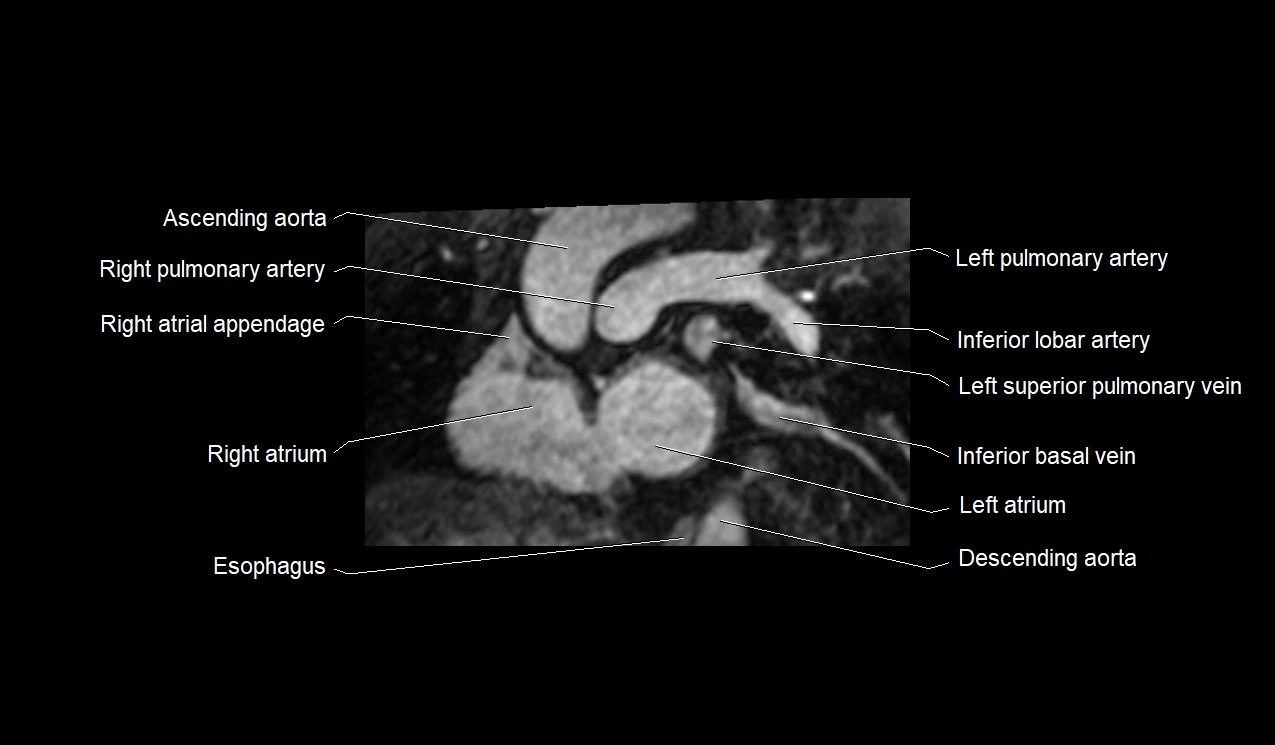

MRI image